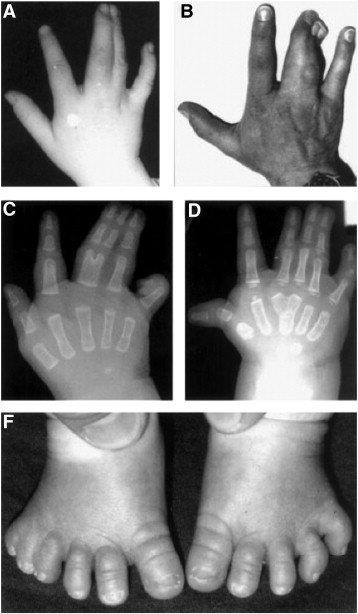

- hoxa13 geni ve hfgs: hfgs, "hand-foot-genital syndrome"un kısaltmasıdır. otozomal dominant bir durumdur. distal falanksın ve/veya ilk metakarpal veya metatarsın kısalmasının neden olduğu bilateral başparmak ve halluks hipoplazisidir. uzuv malformasyonları ve ürogenital malformasyonlar mevcuttur.

- hoxd13 geni ve parmak anomalileri: hoxd13 polialanin ekspansiyonunda parmak anomalileri görülür.